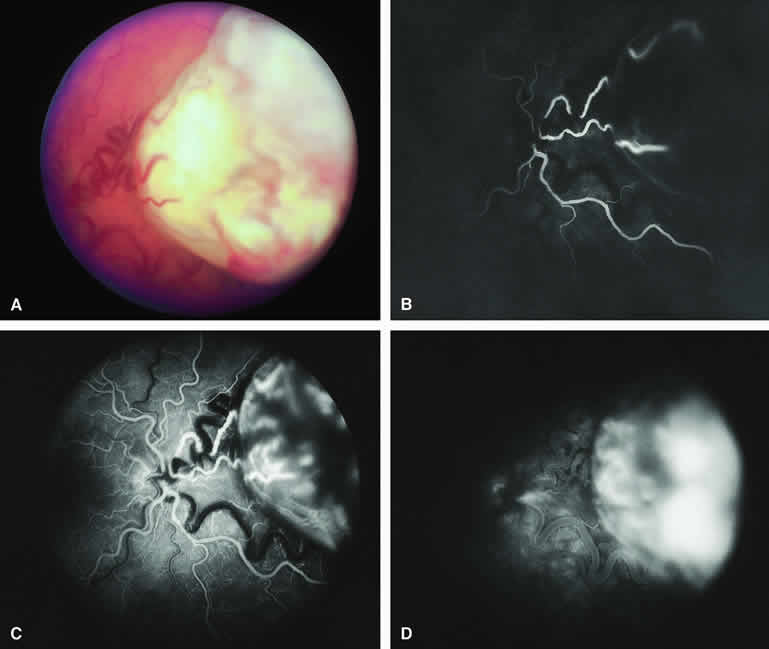

Choroidal Nevus with Drusen and Clumps of RPE Hyperplasia

If a choroidal nevus has drusen and RPE alterations on its surface (see Fig. 4A), fluorescein angiography (Fig. 4B, C, and D) tends to show patchy or stippled window defect hyperfluorescence corresponding to foci of RPE depigmentation, fluorescence blockage by clumps of RPE hyperplasia on the surface of the lesion, and late staining of at least some of the drusen. These features are not usually as evident on ICG angiography as they are on fluorescein angiography.